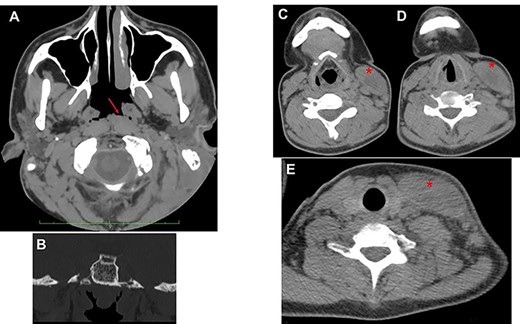

A 17-year-old boy with cognitive-emotional impairment presented in August 2020, to our emergency department, complaining about the onset of a left-sided otalgia with purulent otorrhea, neck stiffness and pain on the ipsilateral side without fever. He had a history of bilateral CCOM for 8 years with recurrent flare-up, which was periodically treated by systemic antibiotic therapy and ear washing with acetic acid due to patient’s refusal of surgery. The patient presented stiffness of the left side of the neck with hot and sweaty skin, associated with hyperemia and swelling in the left latero-cervical region. The inflammation affected the left mastoid region and extended caudally into the left supraclavicular fossa (Fig. 1A).

Pre- and intra-operatory images; (A) purulent secretion from the external left canal associated with swelling of retro-auricular area (mastoid) and neck; the skin is red as a sign of inflammation; (B) after retro-auricular incision and press on the neck, the purulent secretion comes out; (C) a curettage of the neck area is necessary to remove the residual secretion (black asterisk) which has not been expelled through the retro-auricular incision.

The otoscopic examination revealed bilateral perforation of the tympanic membrane and the presence of purulent discharge in the left ear (Fig. 1B). Nasal endoscopy identified II grade adenoid hypertrophy with complete obliteration of left choanal opening and tubal ostium (Fig. 2A and B). A pure tone audiometry, performed only through bone conduction, showed bilaterally normal auditory threshold. Neck ultrasound identified the presence of abundant fluid in the left latero-cervical area, which extended from the retro-auricular region up to the ipsilateral supraclavicular area.

Intravenous therapy with ceftriaxone (2 g every 24 h), metronidazole (500 mg every 8 h), paracetamol (1 g every 8 h) and pantoprazole (40 mg every 24 h) was started because, due to COVID-19 restriction, it was not possible to immediately perform surgery before confirmation of negative COVID-19 swab. Once received the results of the COVID-19 test, we performed mastoidectomy, drainage of neck abscess (Fig. 1C), adenoidectomy and inspection of middle ear.

The purulent secretion was collected from external ear before starting surgery and then from the neck (Fig. 1) after a small incision of the skin and from middle ear during its inspection; all samples were sent to the microbiologist for culture and antibiogram.